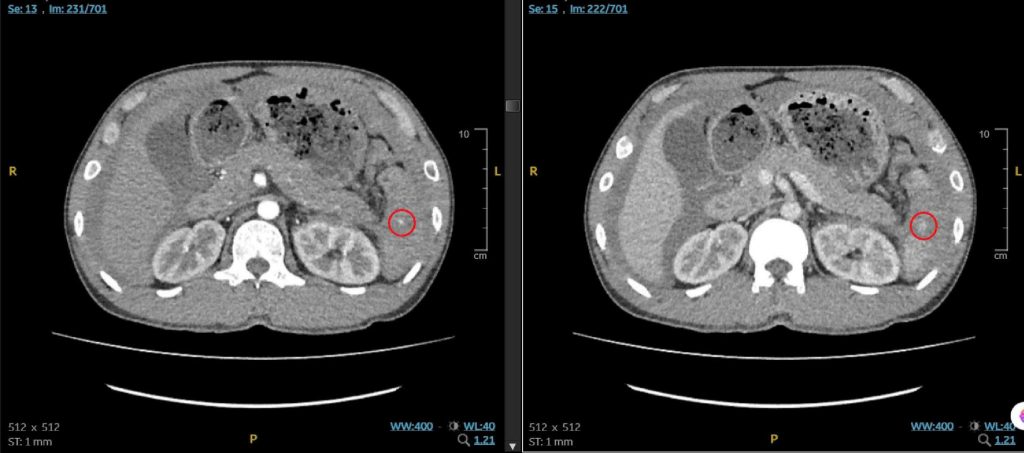

Nghi ngờ nguy cơ chấn thương nội tạng, các bác sĩ lập tức chỉ định chụp CT bụng nhằm đánh giá toàn diện tình trạng chấn thương. Kết quả ghi nhận bệnh nhân bị chấn thương lách độ III, kèm dịch tự do trong ổ bụng – dấu hiệu cảnh báo xuất huyết nội.

Hình ảnh CT vị trí tổn thương, cho thấy vỡ lách